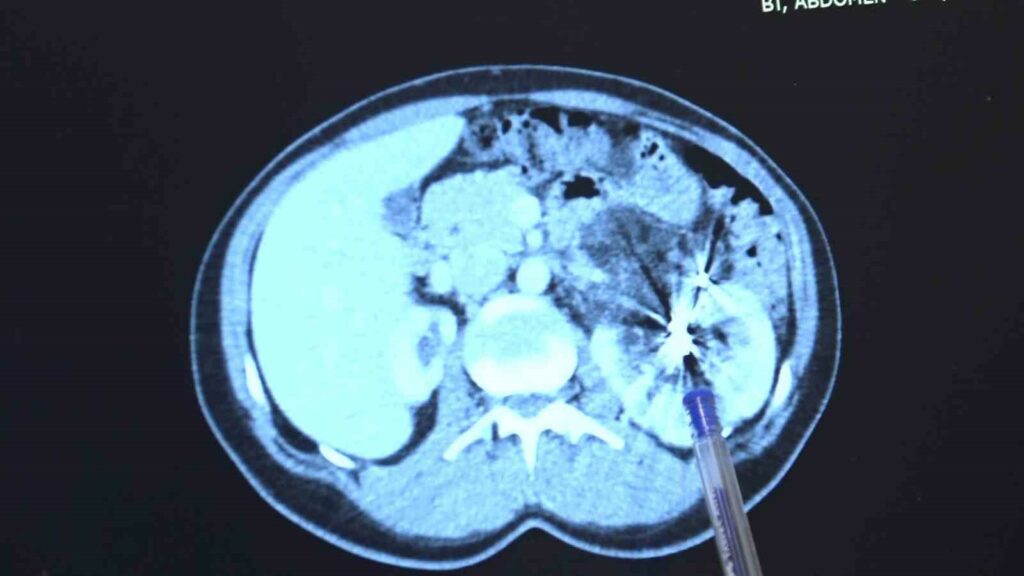

Zorlu bir ameliyatı başarıyla tamamlayan Bursa Medicana Hastanesi Üroloji Uzmanı Doç. Dr. Ahmet Şahan, hastanın durumunun şuan iyi olduğunu belirterek, “Nurcan Hanım 35 yaşında bize İzmir’den geldi. Doğuştan tek böbrekli bir böbreği küçük olduğu için işlevsiz durumda. Sağlam böbreğinde ise 2016’da tanısı konmuş giderek büyüyen iyi huylu “anjiomyolipomu” denilen 12 santimetre boyutunda bir kitlesi var. Bu kitle artık böbreğin damarlarını içerisine almış komplike bir kitle durumunda. Hastaya iki kez anjioembolizasyon tedavisi uygulanmış fakat başarısız olduğu için kitle büyümeye devam etmiş. Kadınlarda 4 santimetreden büyük anjiomyolipomular kendiliğinden kanayarak yaşamı tehlike altına attığı için bu kitlelerin alınması gerekiyor. Tek böbrekli olunan durumlarda böbreğin tamamen alınması durumu da söz konusu olabiliyor. Bu riske girmemek için çoğu merkez de embolizasyona başvurmuş. Hasta bize geldiğinde bu işi yapabileceğimizi söyledik. 2 saat süren kapalı bir ameliyatla kitleyi tamamen çıkardık ve hastamızı 3 gün içerisinde taburcu ettik. Hastamızın değerli şuan iyi durumda. Hastamızı diyalizden kurtarıp kapalı bir ameliyatla sağlığına kavuşturabildiğimiz için çok mutluyuz” dedi.